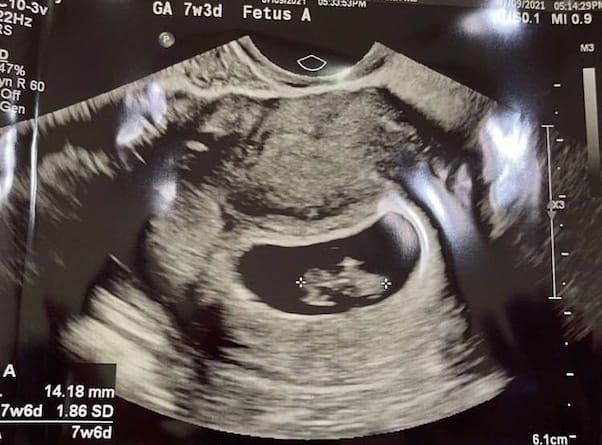

As I implied above, the good news doesn’t stop there! A little under a year after sharing the news that she’d suffered a miscarriage, Brianne made a second reveal post. This time, she shared the good news that she was pregnant again — and that, at the time, Brianne was pregnant with twins!

However, the good news was quickly tempered by a harsh, all-too-common reality. “Chris Riley and I need all the prayers we can get,” Brianne wrote, earlier this summer. “Today I got some results from my last ultrasound Baby B was measuring smaller then baby A so much so they couldn’t get a heart beat count.

“The tech that read my results,” Brianne went on, “thinks baby B is no longer viable because of that…. I saw the baby’s heart flicker telling me there is a heart beat!!!! Praying baby B was just to small to get one. Praying they both grow amazingly and just heal anything that may occur.”

Unfortunately, Brianne has since shared that she lost baby B. (We covered that topic, as well as more baby-related info, in a separate post.) But, Brianne wrote, baby A remains healthy and on track for an early 2022 birthing.